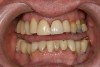

Fig 3. Preoperative condition before functional rehabilitation.

Figure 3